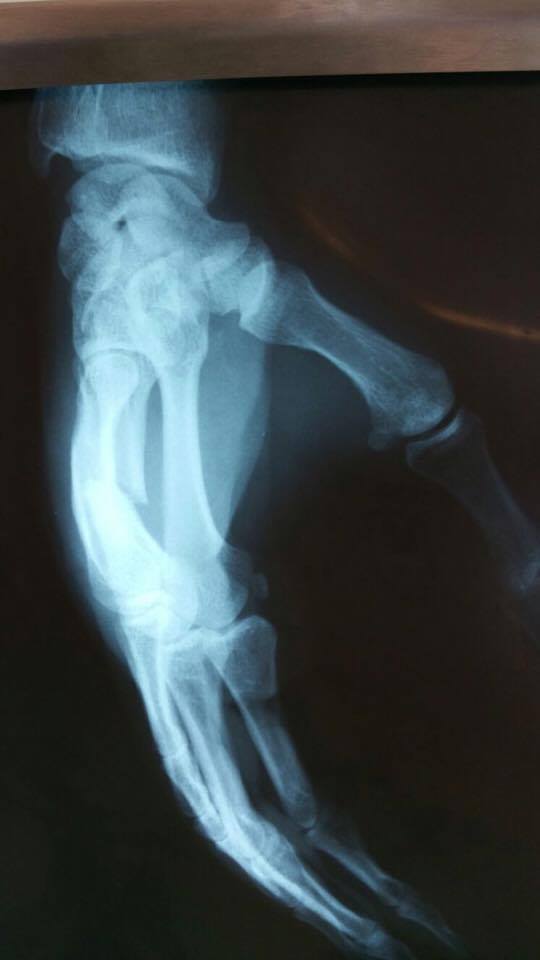

Recent, el a fost implicat intr-o altercatie urata la locul de munca, in urma careia s-a ales cu un o mana rupta si un ghips de toata frumusetea, iar azi va ajunge pe masa de operatii.

Medicii au decis sa ii monteze o tija in mana lui Superman de la Sibiu

„Chirurgii ortopezi au decis sa ma opereze ca sa imi puna oasele de la mana la loc. Am purtat ghips degeaba atata timp. E nevoie de operatie si montarea unei tije si totul e mai grav decat parea la inceput. Sper sa trec cu bine de operatie si refacerea mea sa aiba loc rapid. Trebuie sa muncesc. Am un copil de crescut, sunt tata singur si nu-mi permit sa ma imbolnavesc sau sa fiu accidentat”

, a declarat Cornel Spiridon pentru WOWbiz.ro.